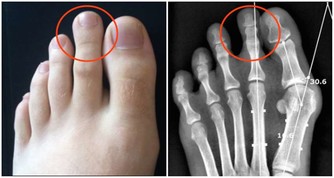

在晚上進餐的時候,對於含有高鈣的食物盡量少吃,比如我們常見的蝦皮等等。因為在夜間時分,我們身體內的五臟六腑會逐漸進入到休息的狀態,這個時候高鈣食物當中的鈣物質就會很容易的沉澱在腎臟以及尿道當中,從而引發腎結石或者是尿結石。